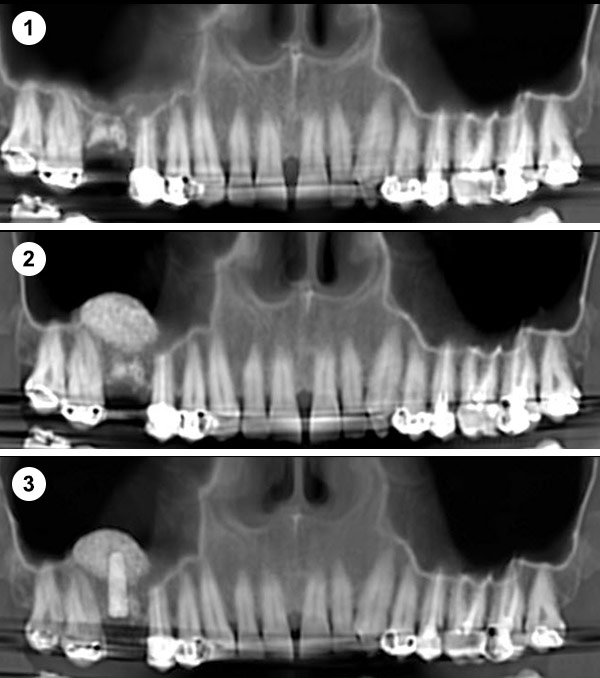

¿Qué material se usa para las elevaciones de seno maxilar?

Se coloca una membrana y un injerto de hueso liofilizado, un compuesto de procedencia bovina que actúa como osteoinductor (Bio-Oss), así una vez colocado induce al hueso a formar nuevas células. Lo que se intenta hoy en día es encontrar una buena calidad de injerto para acortar el período de formación de hueso. También se coloca una membrana sobre este injerto.

Hay muchos biomateriales para inducir la formación de hueso, de distinta calidad y técnica en la elaboración.

En Clínica Sada, utilizamos el mejor biomaterial que científicamente está demostrado para la formación de hueso, Bi-Oss.